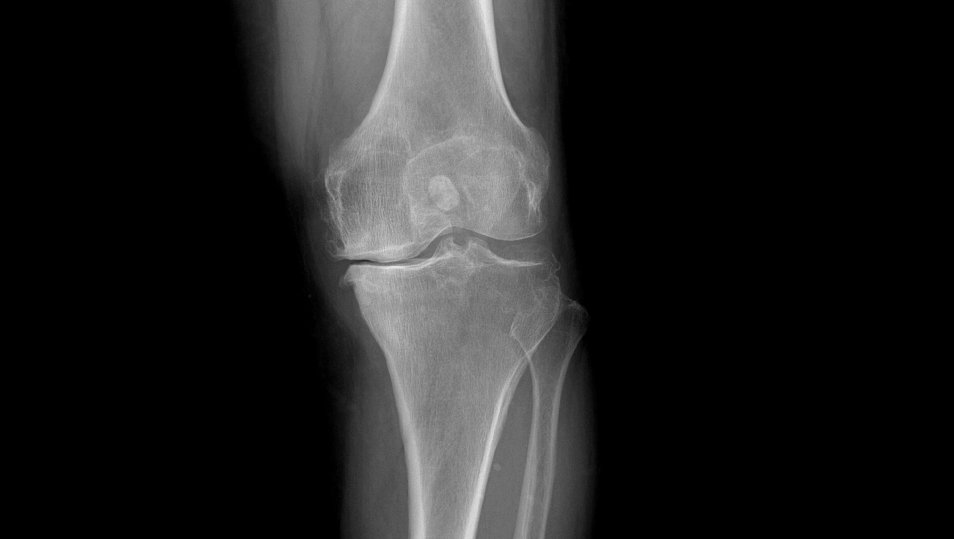

当膝关节由于各种原因,如晚期膝骨关节炎、类风湿关节炎等,导致关节显著破坏,并出现疼痛、活动障碍等症状,通过药物、理疗等手段医治无效时,则可以考虑接受人工膝关节置换手术。

①站立位X光片中显示关节间隙消失或极度狭窄